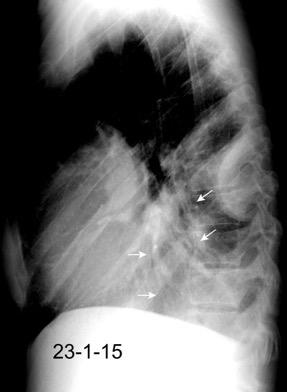

En relación con trasudados tabicados. Insuficiencia cardiaca

Hipoalbuminemia

Cirrosis / Fallo renal.

Operado aneurisma (prótesis). Líquido tabicado en cisuras

Fernandes de Paula MC et al. Focal pleural tumorlike conditions: Nodules and masses beyond mesotheliomas and metastasis. Respiratory Medicine 2015.

Derrame pleural “encapsulado”

“Tumor fantasma”

Asociado a fallo cardiaco. ( “Pleuritis adhesiva”). Buch KP. Chest. 2000